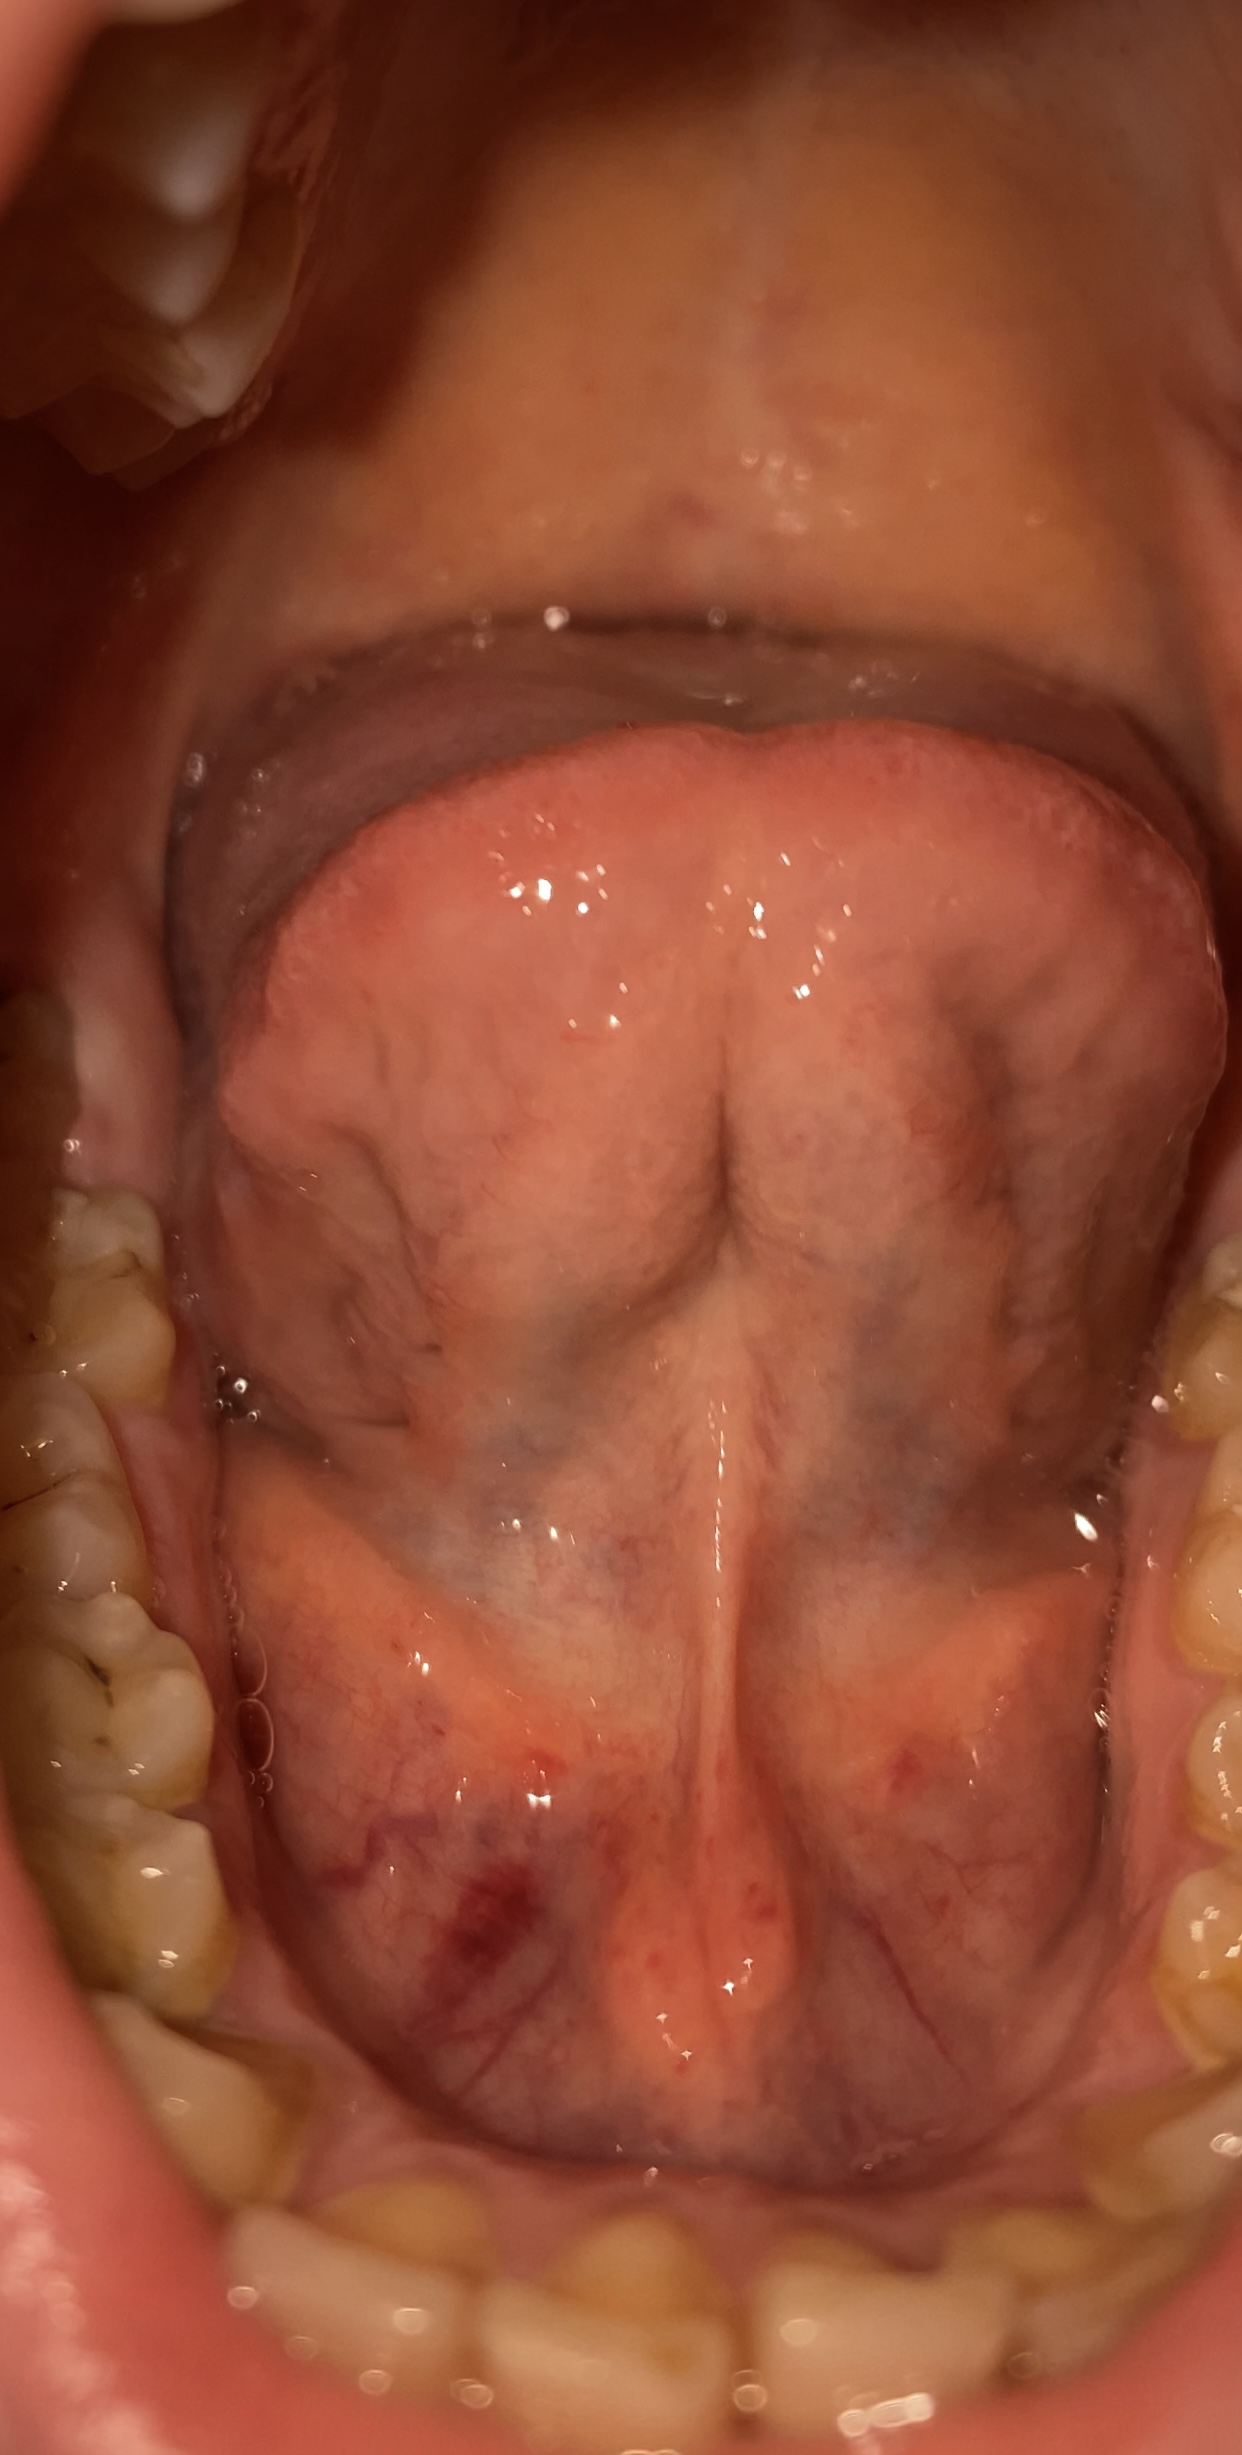

Buongiorno dottori, chiedo qua poiché non so se preoccuparmi, sono una ragazza di 26 anni e stasera ho notato sul pavimento orale una grossa macchia rossa proprio in corrispondenza di una delle vene sotto la lingua, sul pavimento noto che ci sono anche tante piccole macchioline rosse (non so se siano petecchie), non ho cose simili in altre parti del corpo. La macchia più grossa come quelle più piccole non sono "nodulose" al tatto, ne dolorose, infatti me ne sono accorta solamente ispezionandomi allo specchio, cosa che faccio spesso poiché sono abbastanza ipocondriaca, negli allegati inserisco anche una foto fatta circa 15/20 giorni fa dove non avevo nulla di tutto ciò. Premetto che ho già prenotato una visita dal dentista ma non so se dovrei vedere qualche altro specialista. Secondo voi cosa può essere? Grazie in anticipo

Sig. Luana, le nostre mucose non sono stabili ma si modificano continuamente, come il colore del nostro viso. Attenda 15 giorni se il tutto non regredisce spontaneamente e il quadro permane occorre visita presso un odontoiatria che si occupa di patologia orale.